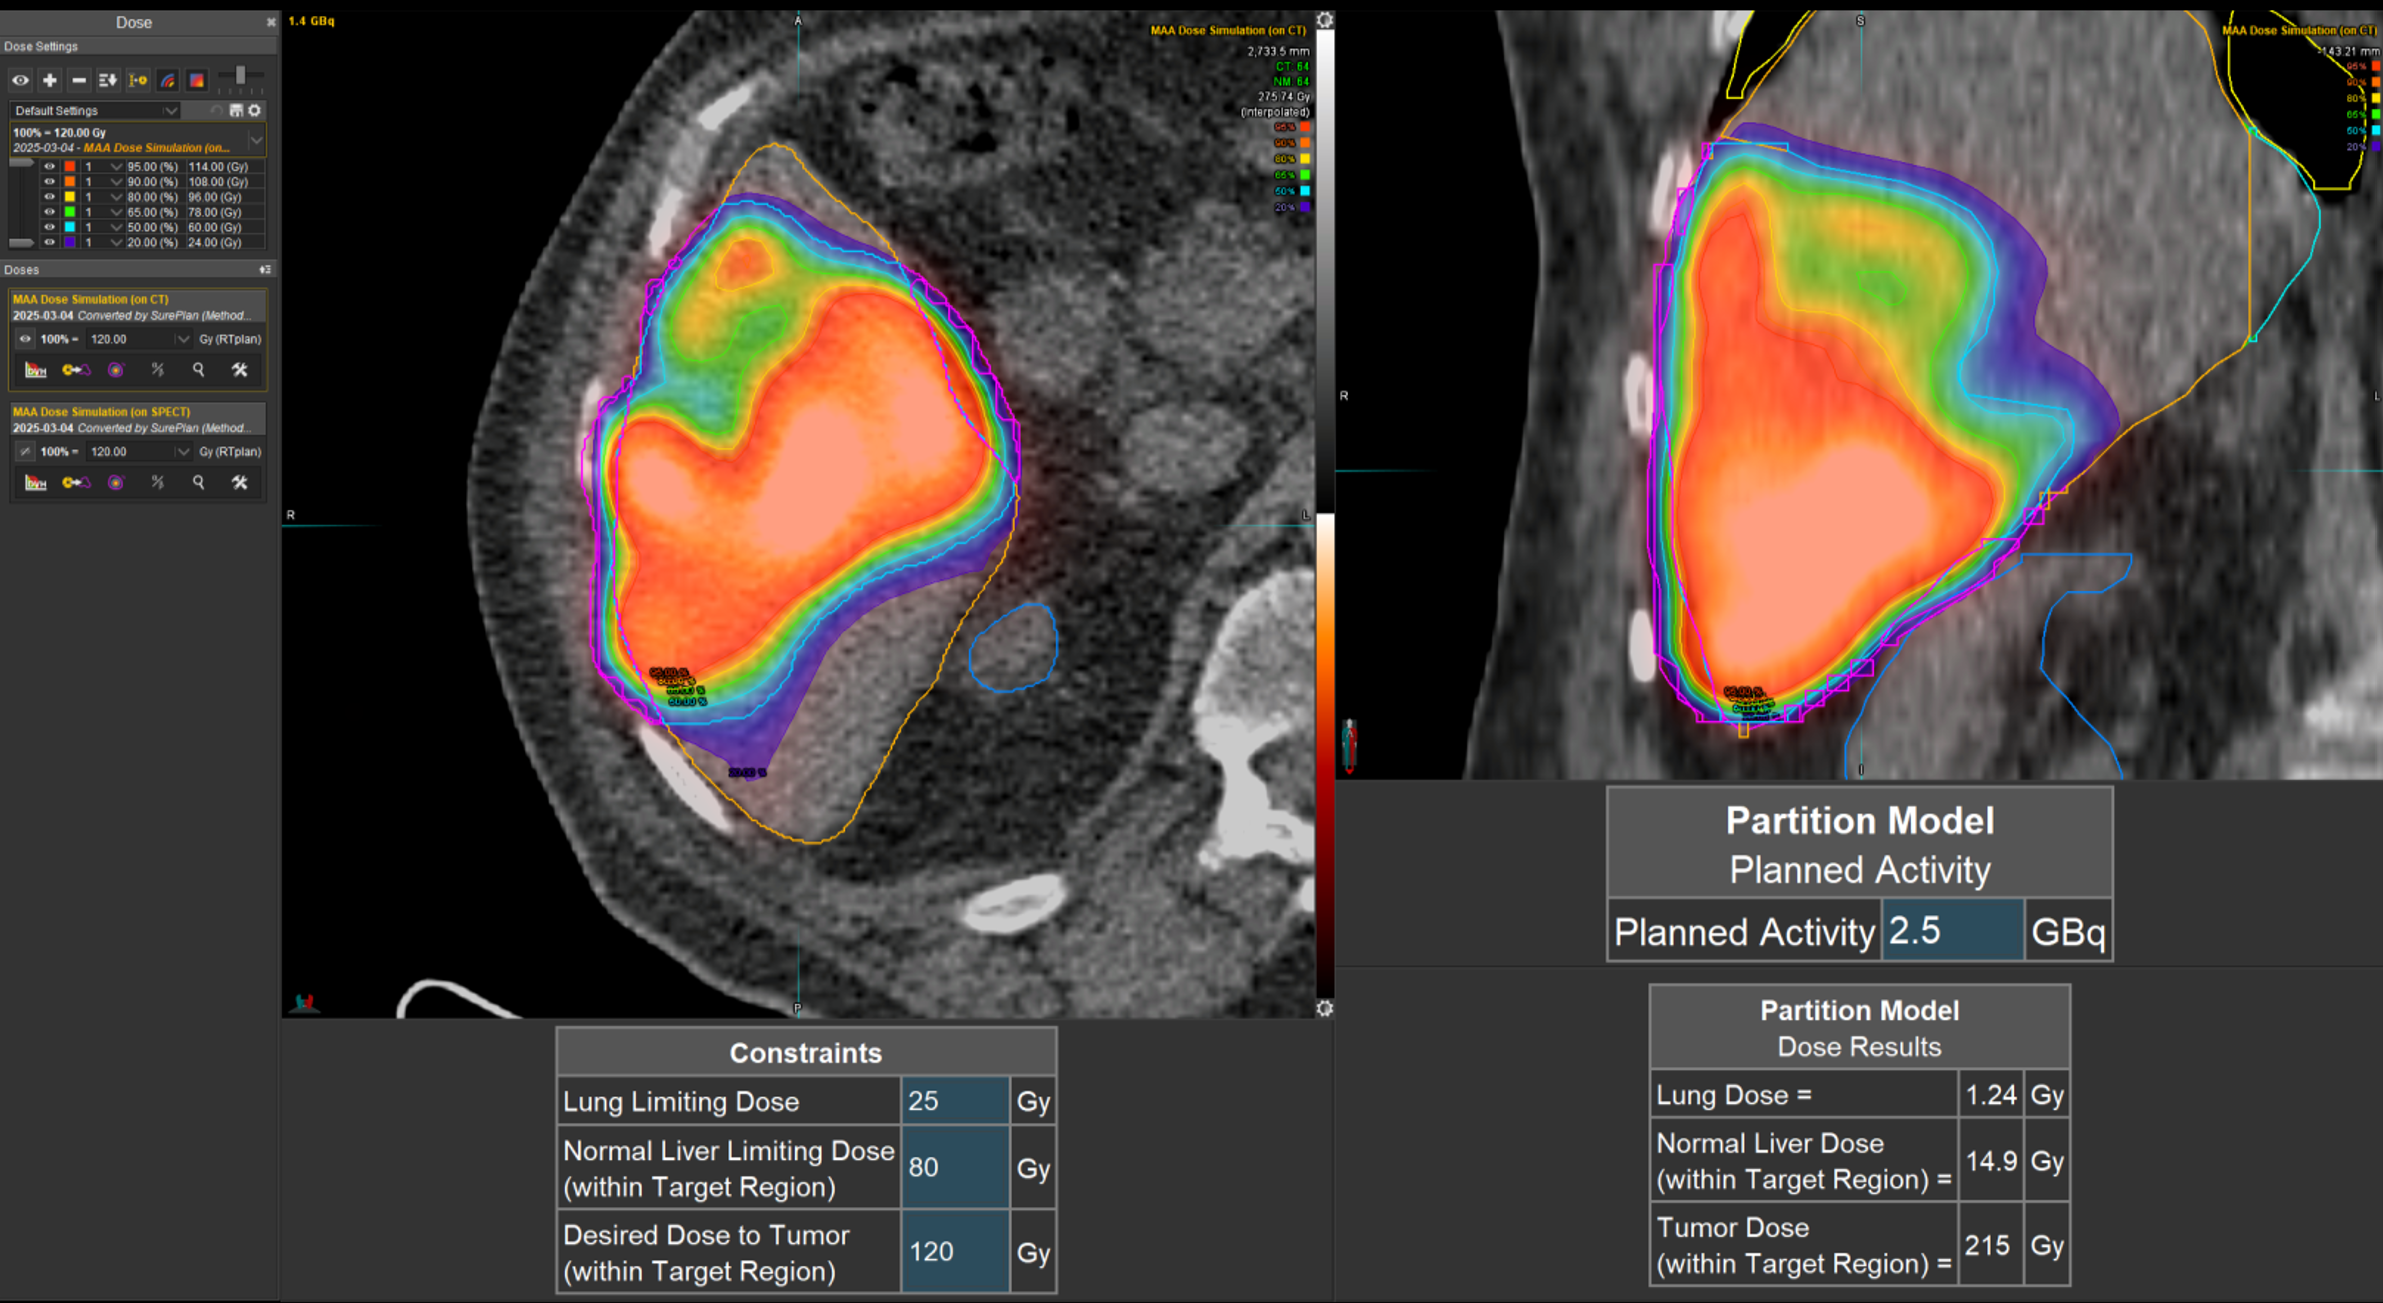

Η θεραπεία με Ύτριο-90 SIR-Spheres (Y-90) αποτελεί μια εξειδικευμένη τεχνική εκλεκτικού ενδοαρτηριακού εμβολισμού, η οποία στοχεύει αποκλειστικά τον όγκο μέσω των ηπατικών αγγείων, επιτρέποντας την εναπόθεση σωματιδίων που εκπέμπουν ραδιενέργεια τοπικά με ελάχιστη ακτινική επιβάρυνση στους υγιείς ιστούς. Η διαδικασία περιλαμβάνει λεπτομερή προθεραπευτικό αγγειογραφικό σχεδιασμό με αξιολόγηση της αγγειακής ανατομίας και χορήγηση ενός ιχνηθέτη για την ανίχνευση τυχόν διαφυγής (πχ. lung shunt), εξασφαλίζοντας μέγιστη ασφάλεια και εξατομίκευση. Η επιλογή της δόσης γίνεται πλέον με σύγχρονα υπολογιστικά μοντέλα δοσιμετρίας και εξειδικευμένα λογισμικά (όπως MIM ή SIR-TeX platform), τα οποία επιτρέπουν ακριβή αποτύπωση του όγκου της νόσου στο ήπαρ, υπολογισμό του πραγματικού tumor burden και εκτίμηση της απορροφούμενης δόσης τόσο στον όγκο όσο και στο υγιές ηπατικό παρέγχυμα. Μετά τη θεραπεία, πραγματοποιείται έλεγχος κατανομής της ακτινοβολίας (μέσω Bremsstrahlung SPECT/CT ή PET/CT), ενώ ακολουθεί στενή απεικονιστική και κλινική παρακολούθηση για την αξιολόγηση της ανταπόκρισης, την εκτίμηση τυχόν τοξικοτήτων και τον σχεδιασμό επόμενων βημάτων στην ογκολογική στρατηγική του ασθενούς. Πρόκειται για μια ιδιαίτερα αποτελεσματική θεραπευτική επιλογή σε πρωτοπαθείς ηπατικούς όγκους και σε ηπατικές μεταστάσεις, ειδικά όταν οι συμβατικές θεραπείες έχουν περιορισμένη αποτελεσματικότητα ή δεν είναι πλέον εφικτές.